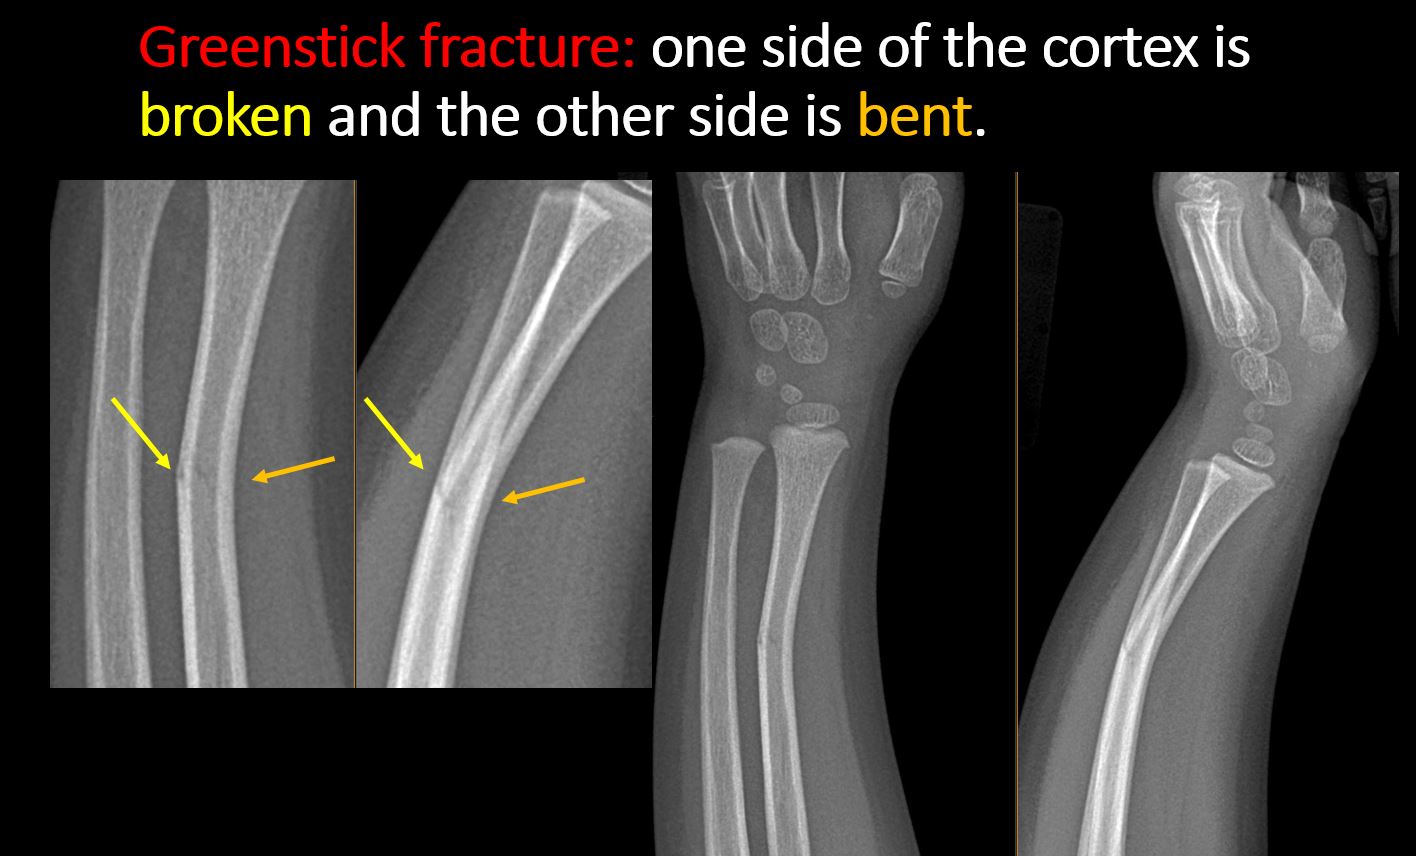

There is a break or interruption of the continuity of the cortical or cancellous bone with or without displacement of a fracture fragment which could be from a greenstick or toddler’s fracture, or other fracture. [Yes/No]